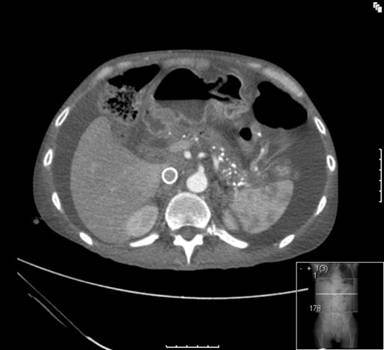

Histopathological analysis of the EUS guided biopsy demonstrated chronic fibrosis and the presence of actinomycosis (Figure 2). No organisms were isolated on culture. He responded well clinically following a course of intravenous antibiotics (tazocin for 30 days) to treat the suspected abdominal actinomycosis. This antibiotic was chosen in accordance with hospital policy. His chylous ascites settled after 2 weeks on home enteral nutrition. His lymphedema subsided and his tumor markers normalized over the subsequent two months. A repeat CT scan at 2 months showed resolution of his portal vein and superior mesenteric narrowing and marked improvement in the caliber of his inferior vena cava (Figure 3). He is on 6 monthly follow-up and is currently symptom free.

Figure 3. CT scan done at 2 months showing complete resolution of pancreatic lesion and showing a metallic stent in place in the inferior vena cava. |